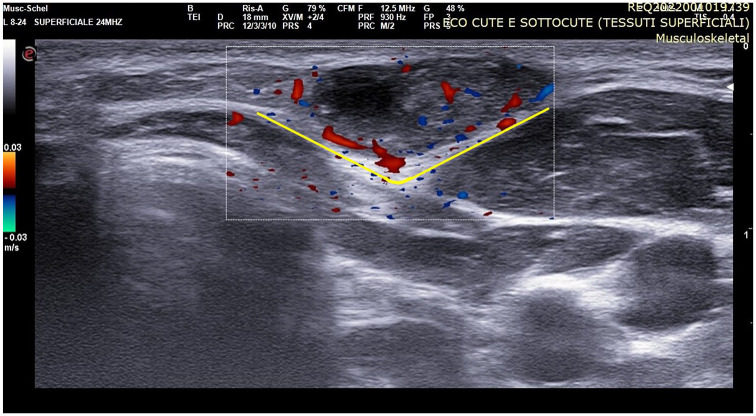

毛瘤是一种罕见的良性肿瘤,起源于头发皮层细胞,在儿童中典型表现为生长缓慢的蓝红色,表面和坚硬的肿块。多发性毛瘤可与基因突变和综合征相关,最常见的是Rubinstein-Taybi综合征、Gardner综合征、肌强直性营养不良症、Turner综合征和Sotos综合征。超声检查可以确定肿瘤的特征,评估深层结构的受累情况,并制定治疗计划。毛囊基质瘤表现出一些独特的超声特征,有助于其诊断,在超声上可视为卵形复杂肿块。毛瘤的并发症和恶性转化已被描述为可能的肿瘤发展,并建议手术切除。我们报告一例罕见的17岁女性智力残疾和小头畸形患者,超声检查显示头颈部有多发毛瘤。患者的综合征特征和基因测试导致鲁宾斯坦-泰比综合征的诊断。我们还关注了鲁宾斯坦-泰比综合征患者毛瘤基质瘤与基因突变之间的关系。

Pilomatricoma is a rare benign neoplasm originating from hair cortex cells and typically manifests in children as a slow-growing bluish-red, superficial and firm mass. Multiple pilomatricomas can be associated with genetic mutations and syndromic disorders, most commonly with Rubinstein-Taybi syndrome, Gardner syndrome, myotonic dystrophy, Turner syndrome, and Sotos syndrome. Ultrasound examination allows this tumor to be characterized, to assess the involvement of deeper structures and to plan treatment. Pilomatricoma shows some distinctive ultrasonographic features that aid in its diagnosis and it may be seen on ultrasound as an ovoid complex mass. Complications and malignant transformation of pilomatricomas have been described as a possible tumor evolution, and surgical resection is recommended. We present a rare case of a 17-year-old female patient with intellectual disability and microcephaly, and with the evidence of multiple pilomatricomas in the head-neck region on ultrasound examination. The syndromic features of the patient and genetic tests led to a diagnosis of Rubinstein-Taybi syndrome. We also focused on the association between pilomatricomas and genetic mutations in patients with Rubinstein-Taybi syndrome.